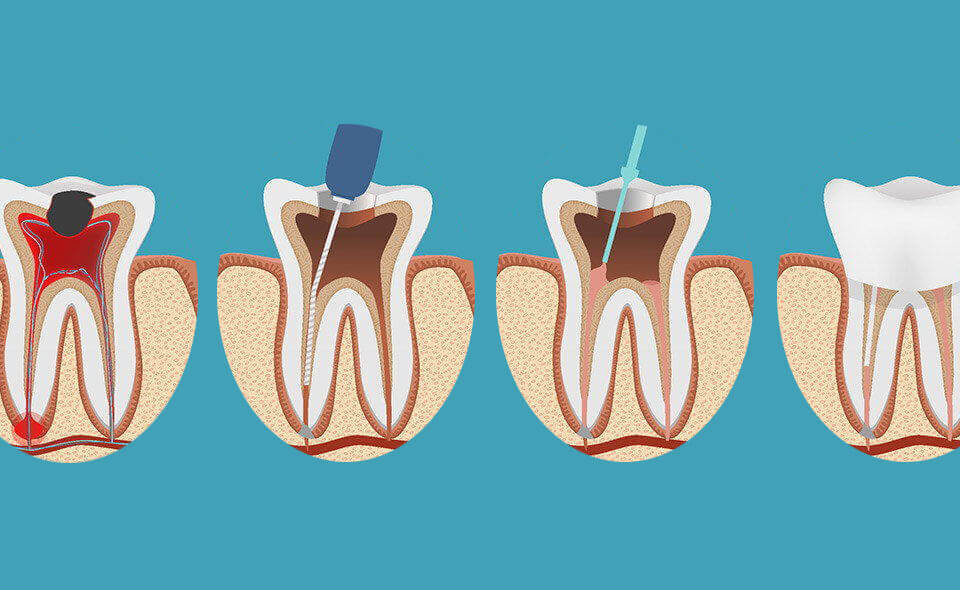

علاج العصب أو ما يُعرف بعلاج جذور الأسنان هو إجراء علاجي دقيق يهدف لإنقاذ السن بدلاً من خلعه عند التهاب العصب أو تضرره الشديد نتيجة التسوس العميق أو الصدمة.يقوم طبيب الأسنان في جدة خلال هذا العلاج بإزالة العصب الملتهب والأنسجة المصابة من داخل قناة الجذر، ثم تنظيف القنوات الداخلية للأسنان وتعقيمها بعناية للتخلص من البكتيريا.بعد ذلك يتم حشو قنوات الجذر بمواد خاصة محكمة الإغلاق لمنع عودة الالتهاب، ثم يُعاد بناء السن وتركيبه بتاج أو حشوة تجميلية للحفاظ على قوته ووظيفته في المضغ والابتسامة.يُعد علاج عصب الأسنان في جدة حلاً فعالاً لتخفيف ألم الأسنان الشديد، وحماية السن الطبيعي لفترة طويلة، ومنع انتشار الالتهاب إلى العظم أو الأسنان المجاورة.يساعد هذا الإجراء على استعادة صحة الفم ويُعد خياراً طبياً موصى به من أطباء الأسنان للحفاظ على السن بدلاً من اللجوء إلى الخلع وخاصة في حالات تسوس الأسنان المتقدم أو التهاب العصب المزمن.

تتم خطوات علاج عصب الأسنان في جدة بطريقة دقيقة ومنظمة للحفاظ على السن وتخفيف الألم بشكل آمن وفعال. يبدأ طبيب الأسنان بفحص سريري دقيق وتصوير بالأشعة لتشخيص حالة عصب السن وتحديد مدى الالتهاب أو التلف. بعد ذلك يقوم بتخدير موضعي للسن لضمان راحة المريض، ثم يفتح تاج السن للوصول إلى قنوات العصب الملتهبة. يتم تنظيف قنوات الجذور بعناية باستخدام أدوات خاصة لإزالة العصب المصاب وبقايا البكتيريا، مع غسل القنوات بسوائل مطهرة لمنع العدوى. بعد الانتهاء من التنظيف والتطهير، تُجفف القنوات جيدًا ثم تُحشى بمادة خاصة لإغلاقها بإحكام ومنع عودة البكتيريا. في الخطوة الأخيرة، يُعاد بناء السن وترميمه إما بحشوة دائمة أو تركيب تاج (كراون) حسب حالة السن لضمان متانته ووظيفته على المدى الطويل. الالتزام بهذه الخطوات المتكاملة في علاج عصب الأسنان في جدة يساعد على إنقاذ السن الطبيعي وتخفيف الألم والحفاظ على صحة الفم والأسنان.